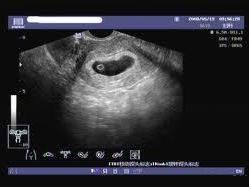

在孕早期后期或孕中期,通過B超應(yīng)能檢測到胎兒心跳,如無法檢測到胎兒心跳,可能是空孕囊的征兆。

通過B超檢查發(fā)現(xiàn)胚胎未按照正常時間發(fā)育,如未按時出現(xiàn)胚芽、胎心等,可能是空孕囊的表現(xiàn)。

羊水是胎兒生長的重要環(huán)境,如B超檢查發(fā)現(xiàn)羊水過少或無羊水,可能是空孕囊的征兆。